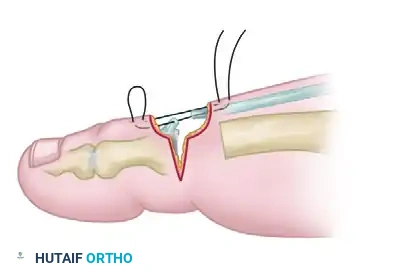

Next, address the rigid PIP joint contracture of the second toe:

* Approach the second toe PIP joint through a dorsal elliptical incision. This incision design allows for the excision of redundant dorsal skin, creating a "dermodesis" effect that assists in maintaining extension.

- Incise the dorsal capsule and collateral ligaments of the PIP joint.

- Elevate the extensor tendon proximally. Perform a resection arthroplasty by removing the distal one-third of the proximal phalanx using a microsaw or bone rongeur.

- Ensure enough bone is resected so that the toe can be held in a neutral position at the PIP joint without any bony impingement.

- Closure and Dermodesis: Hold the joint in the proper position (0 to 15 degrees of flexion). Pass a suture through the skin and tendon, back through the tendon and skin, and tie it in a reverse skin-to-skin mattress configuration. This secures the dermodesis and stabilizes the resection arthroplasty.